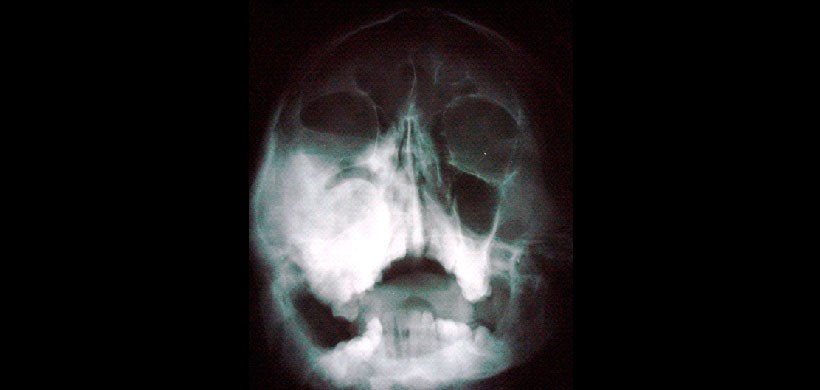

Figura 7: Vista Posteroanterior muestra una asimetría de la región maxilofacial.